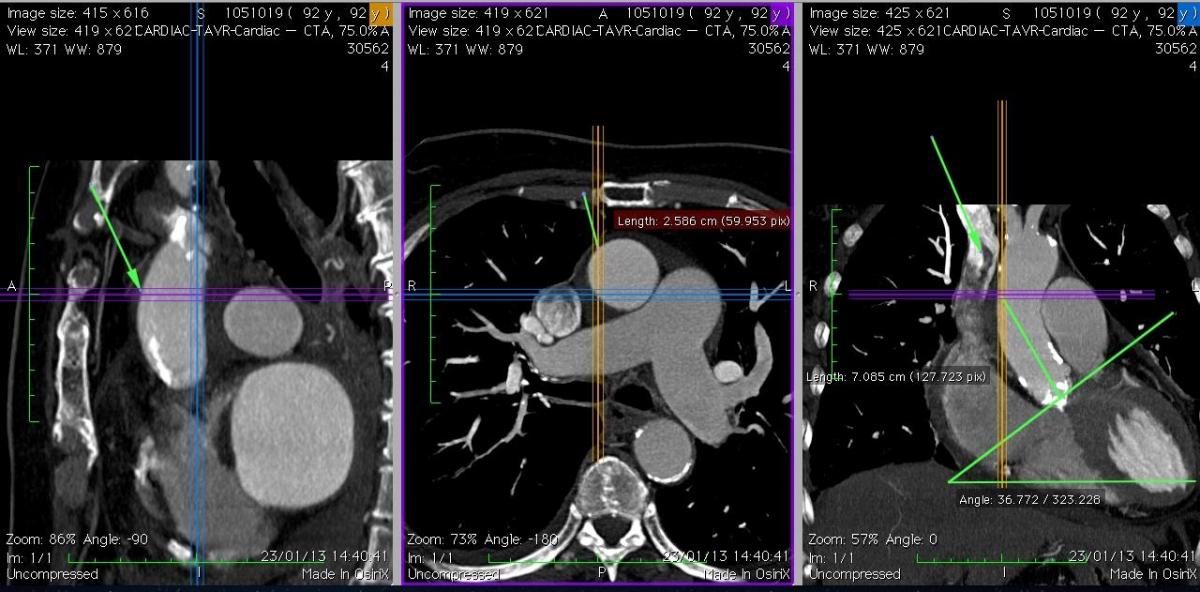

4. Trans-Aortic Valve Replacement with Edwards Sapien-Ascendra 3 Mark Russo Paolo Tartara |